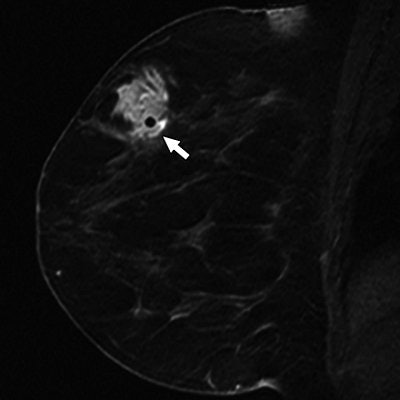

60-year-old woman with history of left mastectomy presents for follow-up MRI examination of right breast with normal mammogram and normal physical examination. Above, sagittal fat-suppressed image of right breast after contrast injection immediately before biopsy confirms presence of mass (arrow). Below, sagittal fat-suppressed image of right breast immediately after 9-gauge MRI-guided vacuum-assisted biopsy shows obturator (arrow) in high-signal hematoma obscuring biopsy site.